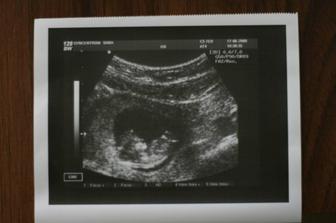

♥ dne 26.5.2008 UTZ u mého gynekologa, mrňousek krásně roste – máme 1,42 cm a jsem 7tt+6

♥ dne 17.6.2008 další KO a UTZ, vše je v pořádku, mrňousek si cucá prstíky, nadskakuje jak na trampolíně a nakonec nám zamával 🙂, váha maminy 58kg